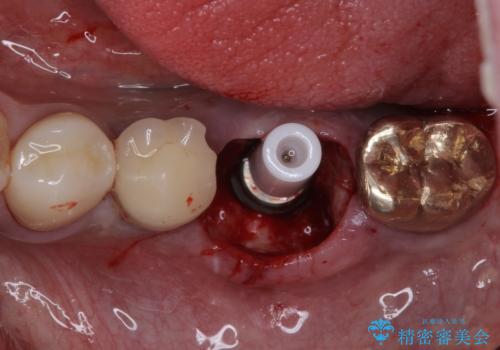

そのため、当院に新しく導入した手法により、抜歯をした日にインプラントを埋入し、そのままを仮歯を装着することで、他の歯への負担を軽減する計画を立てました。

インプラント埋入時に植立具合の安定性を測定したところ、十分な数値が得られたため、速やかに仮歯を装着して咬合回復をさせることができました。

抜歯を含めた外科処置を1回に抑えることができ、あっという間に治療を終えることができました。